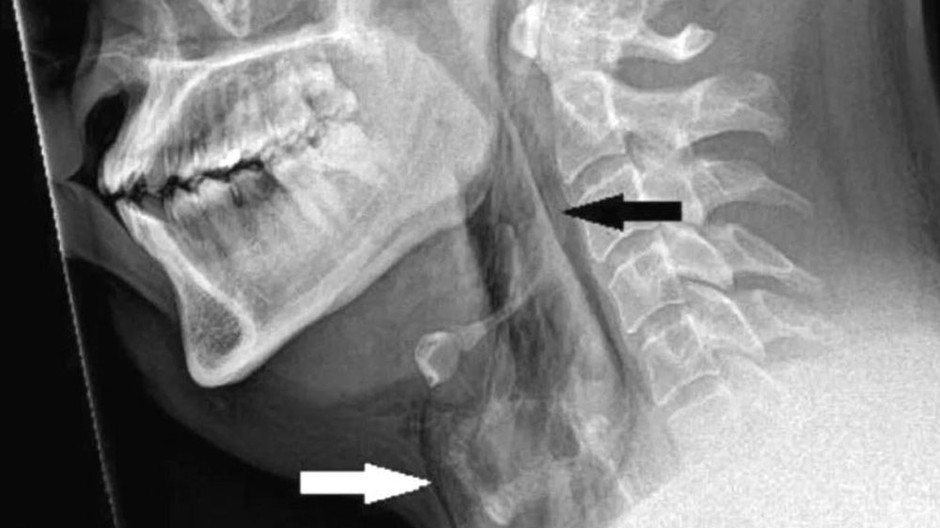

Tridsaťročný pacient bol v silných bolestiach prevezený do nemocnice Ninewells v škótskom Dundee. Testy odhalili, že utrpel 2 milimetrovú trhlinu v priedušnici, pretože si pri kýchaní držal nos a zavrel ústa, informuje BBC.

Nemocničné testy odhalili 2 mm perforáciu v priedušnici.

Aj v Spojenom kráľovstve v roku 2018 boli lekári privolaní k ošetreniu 34-ročného muža, ktorý si pretrhol priedušnicu, keď sa snažil potlačiť silné kýchnutie. Muž uviedol, že počas kýchnutia zažil pocit "prasknutia" a potom okamžite pocítil ostrú bolesť v zadnej časti hrdla, ktorá mu sťažila prehĺtanie a hovorenie. Keď ho lekári vyšetrili, zistili opuch a citlivosť v oblasti hrdla a krku a röntgenové vyšetrenie ukázalo, že vzduch uniká z priedušnice cez trhlinu v mäkkom tkanive krku. Muž musel byť nasledujúcich sedem dní vyživovaný cez hadičku, aby sa tkanivo mohlo zahojiť, a po týždni v nemocnici sa úplne zotavil.